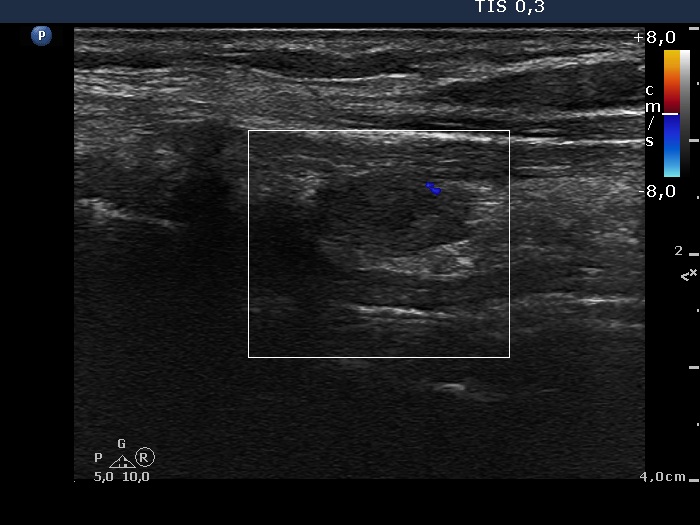

Second examination - 3 years after surgery (2nd row of images)

Ultrasonography: the right thyroid was minimally-moderately hypoechogenic and enlarged and contained several hypoechogenic areas. The resected left lobe was moderately hypoechogenic.A replacement therapy with 50 microgram levothyroxin was started.

Three years after surgery the right thyroid became enlarged because it had to take over the hormon production of the resected left thyroid.